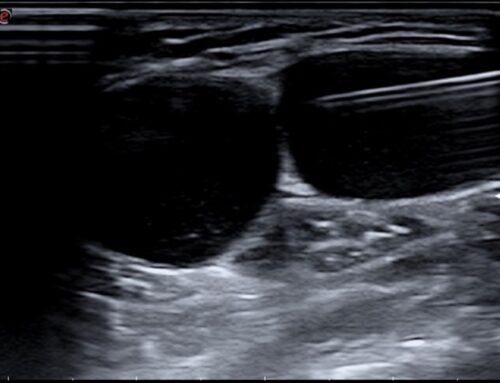

El lavado ecoguiado de calcificación es una técnica mínimamente invasiva destinada a tratar la tendinitis calcificada del hombro u otras localizaciones. Consiste en introducir una fina aguja guiada por ecografía hasta la calcificación y realizar un lavado con suero para fragmentarla y extraerla parcialmente. El objetivo es reducir la presión dentro del tendón y disminuir la inflamación. Es una alternativa eficaz cuando el dolor limita el movimiento o persiste pese a otros tratamientos.

• La guía ecográfica permite actuar exactamente sobre la calcificación, aumentando la precisión y disminuyendo riesgos.

El paciente se coloca en una posición cómoda y se limpia la piel. Se administra anestesia local para evitar molestias. Con la ayuda del ecógrafo se localiza la calcificación y se introduce una aguja fina para realizar el lavado con suero. En ocasiones se complementa con una pequeña infiltración antiinflamatoria. El procedimiento dura entre 10 y 20 minutos. El paciente suele notar solo presión o molestia leve.

Es una técnica muy segura. Puede aparecer dolor moderado en las primeras 24–48 horas, hematoma pequeño o leve inflamación local. Las complicaciones importantes son raras. La ecografía permite evitar estructuras sensibles como vasos o nervios, aumentando la seguridad. El procedimiento lo realiza un especialista con amplia experiencia en intervenciones ecoguiadas.